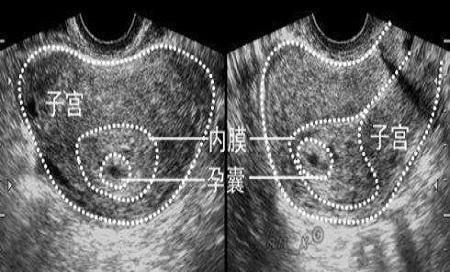

只要不是孕囊在正常的子宫腔内,均属异位妊娠,也是大家俗称的宫外孕.

宫腔内的小孕囊.